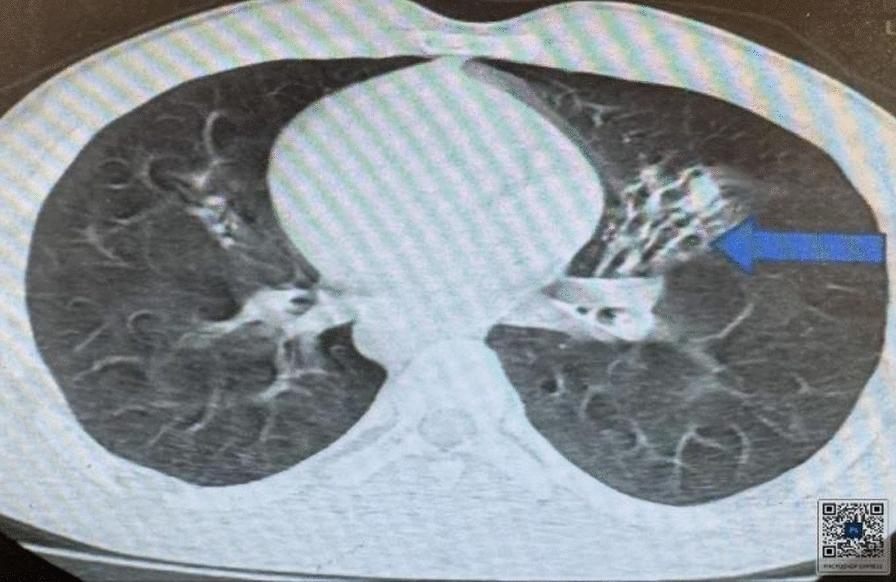

This case involved a 17-year-old Black African Semitic male patient who presented to our hospital with a complaint of intermittent productive cough, which started when he was 5 years old. He had a history of repeated treatment for lower respiratory tract infection and chronic sinusitis with frequent exacerbation. On examination, he had coarse crackles over the left posterior lower lung field. Heart sounds were appreciated on the right side. During imaging investigations, his chest X-ray posterior-anterior view showed dextrocardia and right side gastric shadow with left paracardiac bronchiectatic changes. A high-resolution chest computed tomography scan was suggestive of complete situs inversus. There were left lower lobe bronchiectatic changes. An electrocardiogram showed features of dextrocardia. Routine laboratory tests were within normal range. He was treated with thoracic physiotherapy, azithromycin 500 mg three times per week, and mucolytics, with no apparent exacerbations in the last 6 months.

该病例涉及一名17岁的黑非洲闪米特男性患者,他因间歇性咳痰前来我院就诊,这种情况始于他5岁时。他有下呼吸道感染和慢性鼻窦炎反复治疗史,且频繁加重。检查时,左后下肺野可闻及粗湿啰音。心脏听诊在右侧。影像学检查中,他的胸部后前位X线片显示右位心和右侧胃泡影,伴有左心旁支气管扩张改变。高分辨率胸部计算机断层扫描提示完全性内脏转位。有左下叶支气管扩张改变。心电图显示右位心特征。常规实验室检查在正常范围内。他接受了胸部物理治疗、每周三次500毫克阿奇霉素以及黏液溶解剂治疗,在过去6个月中没有明显加重。